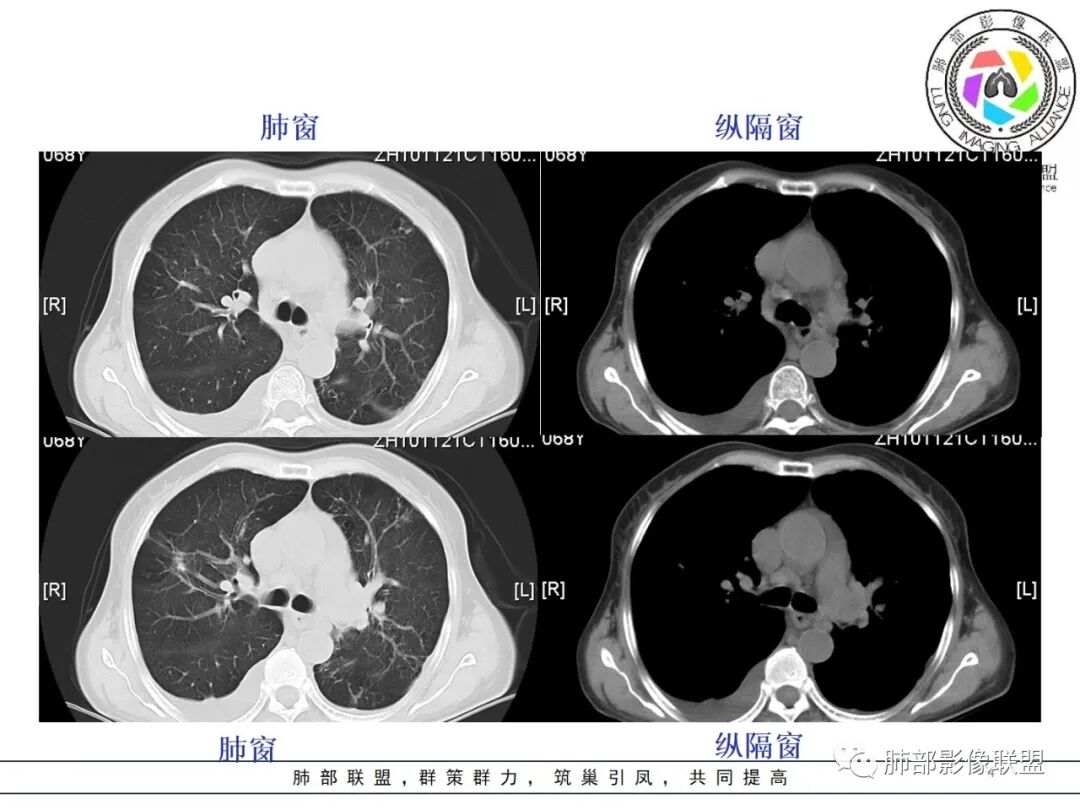

杨丽:

老年女性,肺气肿背景。右肺上叶不规则肿块,局部膨隆,有边界清晰磨玻璃影,细长毛刺,胸膜牵拉,收缩力中等,外朝内生长,后段部分支气管似闭塞,不均匀较明显强化,坏死边界欠清;近八年复查明显增大。考虑腺癌可能性大,鉴别结核。

王开金江津中心医院呼吸科:     老年女性,痰血,右肺新生物,毛刺,分叶,胸膜凹陷,支气管截断,空炮,周围有部分磨玻璃,淋巴结肿大,结合肿瘤标志物升高,考虑肺恶性肿瘤,倾向腺癌。鉴别结核。

红星:    女性68岁,右肺上叶前段结节,将近7年的时间明显长大,表现出分叶毛刺及支气管截断伴胸膜凹陷,增强明显的不均匀强化,纵隔内多发的淋巴结肿大。左肺多发的斑点及条索状间质改变。考虑右肺上叶前段恶性病变,腺癌的可能性大。鉴别诊断结核或炎性肉芽肿。

宇宙:  右肺上叶不规则肿块,较8年前结节明显增大,可见分叶,毛刺,胸膜牵拉,边缘清晰磨玻璃影,上叶后段支气管堵塞,不均匀延迟强化,有坏死,纵隔淋巴结增大,考虑恶性,腺癌,鉴别炎性肉芽肿

孔儿 :   老年女性,右肺上叶前段结节8年复查明显增大,收缩力强,分叶,毛刺,邻近胸膜牵拉,部分支气管截断,周围见边界清晰磨玻璃成分,增强扫描呈不均匀强化,考虑恶性肿瘤,浸润性腺癌可能性大。

刘强:   老年女性,右肺上叶不规则肿块,月牙铲,有收缩,分叶,毛刺,近8年后结节明显增大,边缘清晰磨玻璃影,上叶后段支气管堵塞,不均匀延迟强化,有坏死,纵隔淋巴结增大,考虑恶性,腺癌可能性大

Yishion:   时间跨度虽然大,但原病灶增大,常规需要考虑恶性肿瘤,支气管截断,不符合淋巴瘤,时间太长,说明病灶相对生长过慢,如果是鳞癌,一般破坏力很强,8年时间很难支撑得下来,常规考虑腺癌

蓝天白云:    老年女性,右肺上叶不规则肿块,月牙铲,有收缩,分叶,毛刺,边缘清晰的磨玻璃影,上叶后段支气管截断,胸膜牵拉凹陷,不均匀延迟强化,内见空泡,纵隔淋巴结增大,IAC。所以的恶性征象都有了

丽:    病灶八年明显增大,右肺上叶不规则肿块,边缘毛刺、分叶,胸膜牵拉,并可见清晰磨玻璃密度影,临近支气管截断,增强后不均匀强化,内可见多发低密度,纵膈肿大淋巴结,考虑恶性,常规考虑腺癌

飞鹰行动:   老年女性,右肺上叶前段结节8年复查明显增大,收缩力较强,有分叶,长短毛刺,邻近胸膜受牵拉,部分支气管截断和受牵拉,周围见边界清晰磨玻璃成分,增强扫描呈不均匀强化,内部低密度区可见磨玻璃强化,边缘模糊,考虑恶性肿瘤,腺癌可能性大。鉴别结核,后者强化不明显,支气管牵拉后扩张。

任广国:    病灶发展8年,从混合磨玻璃密度到实性肿块,毛刺分叶明显,胸膜牵拉,(收缩力较强),中等度强化

1、老年女性,肺气肿背景,咯血多年,肿瘤标志物升高。    2、右肺上叶不规则结节影,八年后进行性增大为肿块,边缘深分叶、毛刺、棘状突起、胸膜牵拉,相应支气管壁增厚阻塞;周围局部见边界清楚的磨玻璃影;近胸壁侧见凹陷,整体呈外朝内生长。增强扫描呈不均匀明显强化,其内见坏死区,边界欠清。    3、右侧胸腔积液。纵隔见增大淋巴结。

影像及临床符合肺腺癌的诊断。8年的时间为我们展示这样一个生长过程,还是具有一定程度参考意义的。